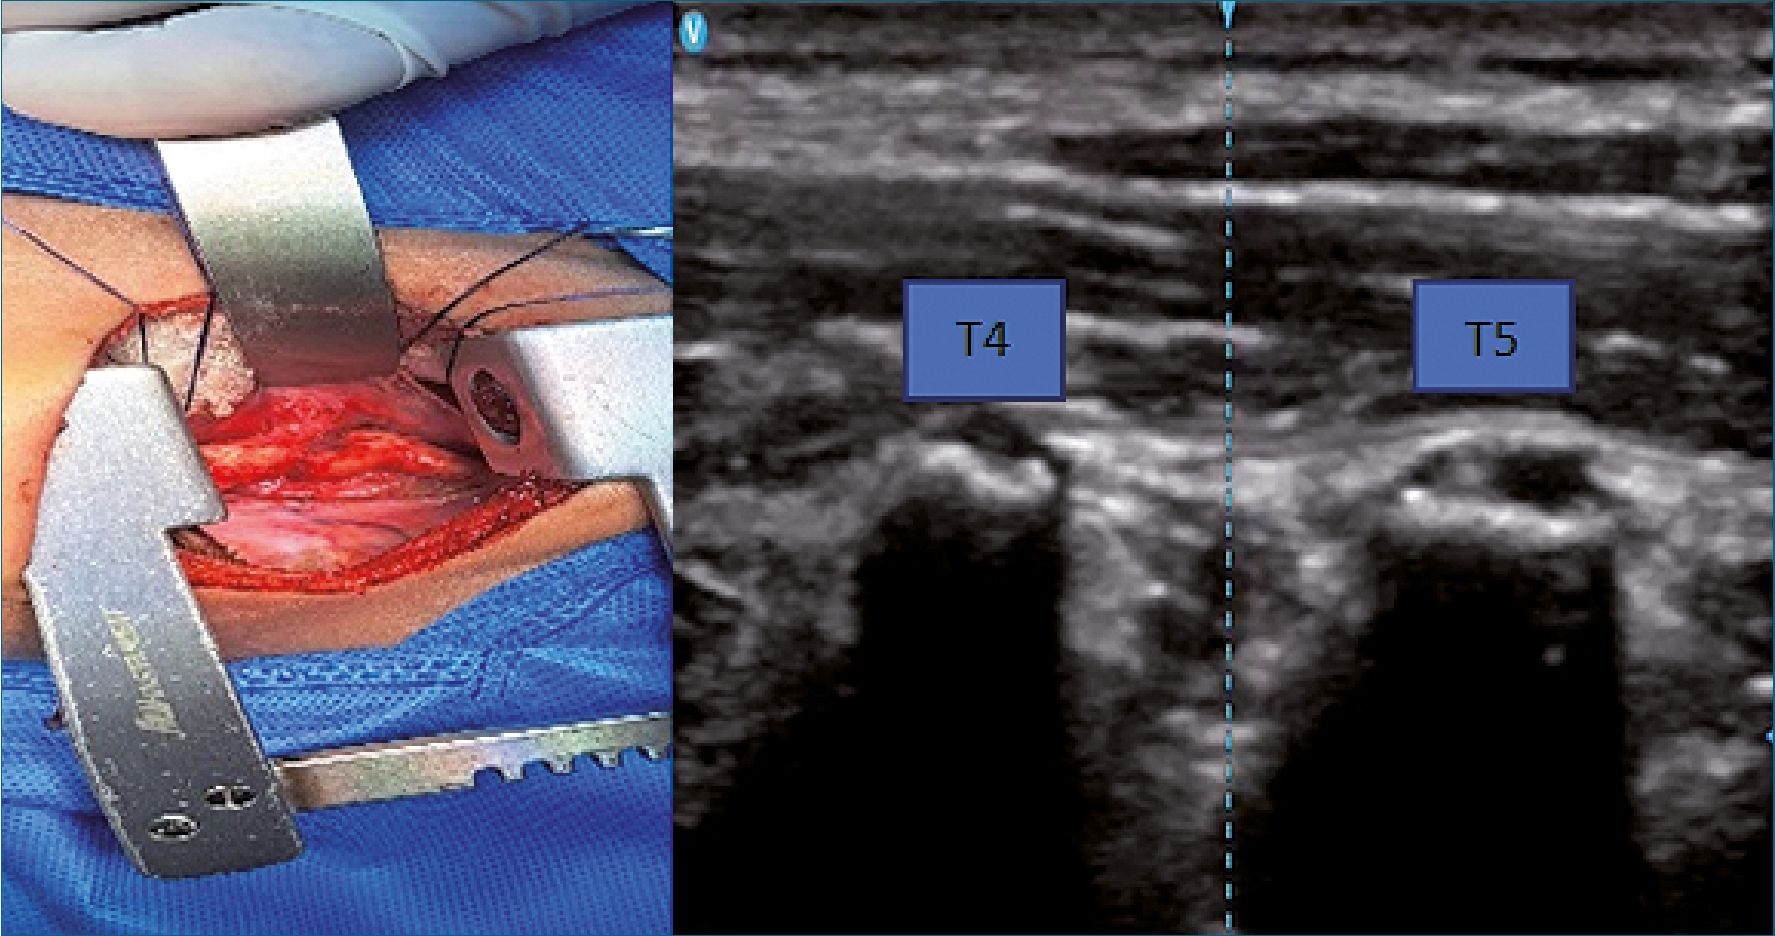

Técnica de bloqueo del plano erector de la espina (ESP)

El bloqueo del erector de la espina se realizó bajo normas de asepsia y antisepsia, con la utilización de un sistema ecográfico portátil, dispositivo de ultrasonido (Vscan AirTM, GE Healthcare), el procedimiento se ejerció posterior a la inducción anestésica y fue colocado en decúbito lateral derecho, se identificó la quinta apófisis espinosa torácica (T5). Se colocó el transductor lineal parasagital a la apófisis espinosa de T5 y paralelamente se mueve la sonda de lateral a medial sobre la apófisis transversa identificado por su aspecto cuadrado. El músculo trapecio, romboide mayor y el músculo erector de la espina podrían reconocerse superpuesta a la protuberancia transversal hiperecoica. Se insertó una aguja ecogénica para bloqueo anestésico de calibre 22G (50 mm) se enfoca en dirección caudal-cefálica hasta que la punta queda en la profundidad del músculo erector de la columna y golpea la apófisis transversa; se administra un volumen de 0,5 ml.kg-1 de bupivacaína sin epinefrina al 0,25% juntamente con lidocaína al 2%. El bloqueo se realizó en el lado del abordaje de la toracotomía y bilateral en el caso de esternotomía (Figura 1).

Figura 1. A) Toracotomia lateral izquierda; B) Sonoanatomia músculo trapecio (TM), músculo romboides (RM), erector espina (ESP), procesos transversos T4 y T5; C) Abordaje del bloqueo.